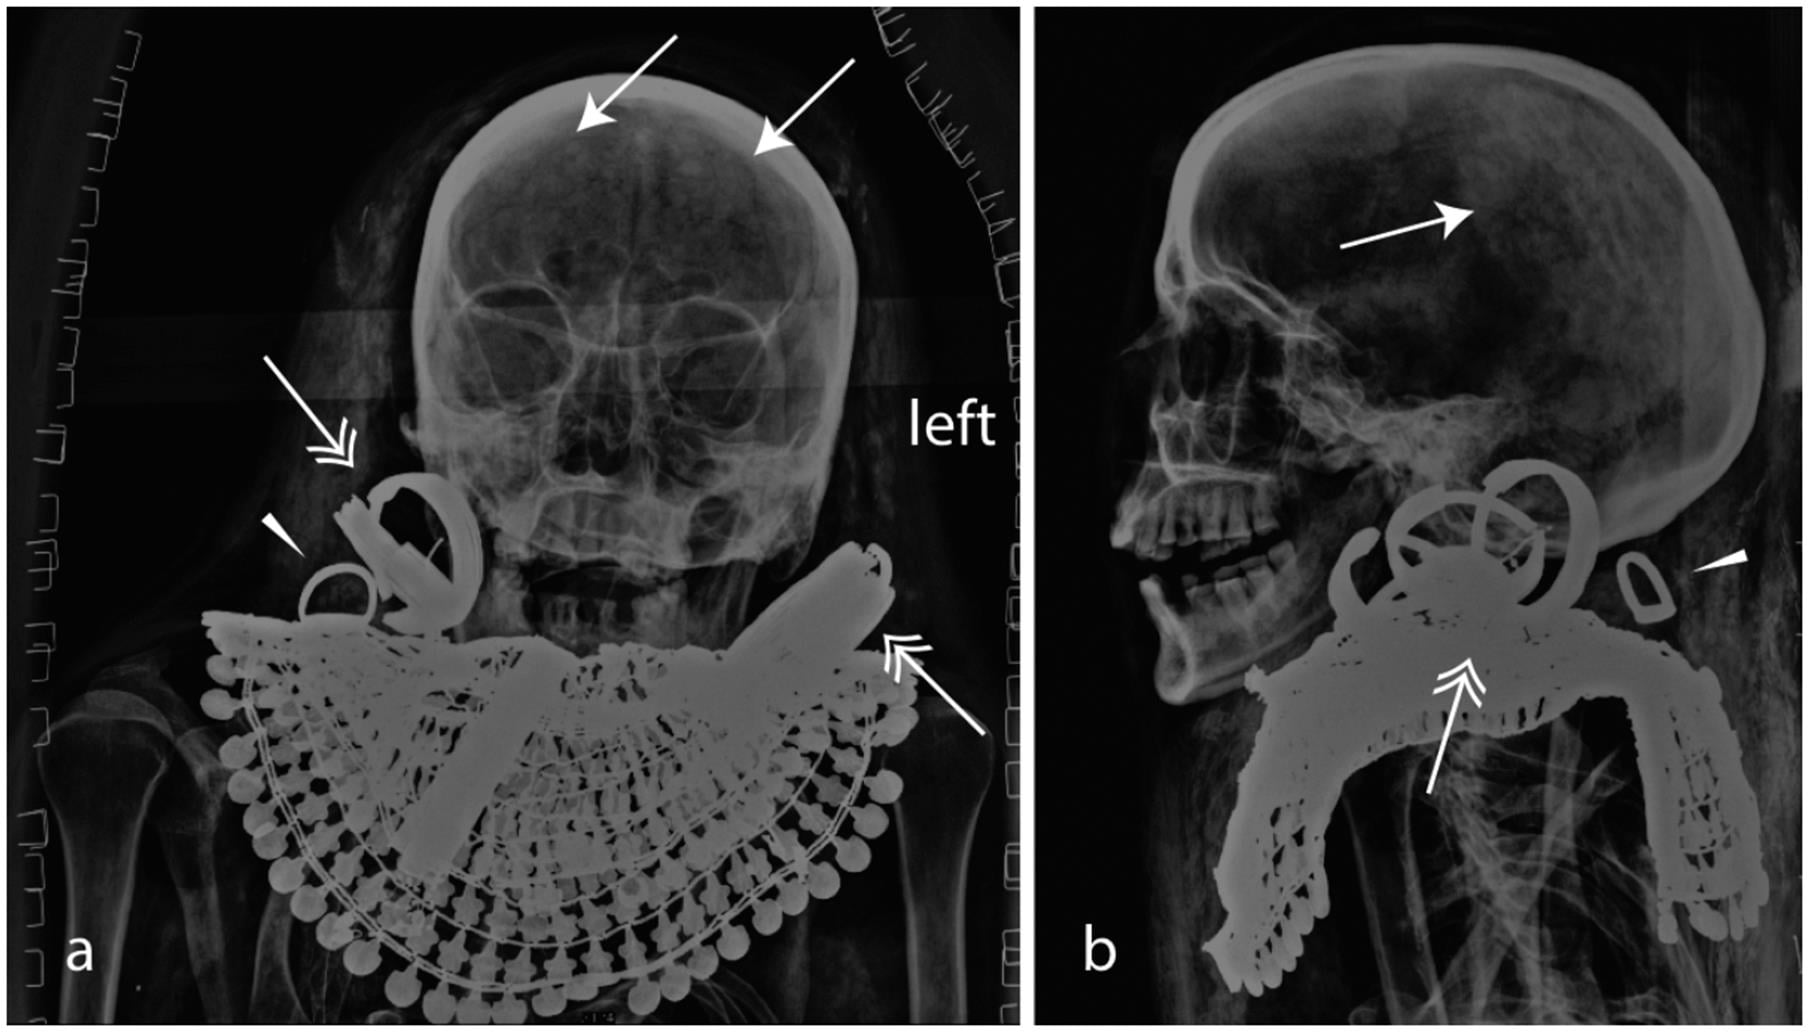

Le mummie non sono mai state sbendate; la mummificazione sarebbe avvenuta per semplice immersione in bagno di natron (non ci sono segni di eviscerazione, quindi non ci sono vasi canopi per la conservazione degli organi interni).Le mummie furono esaminate ai raggi X negli anni ’60, e la conclusione fu che, nonostante lo status di Kha e Merit, la mummificazione fosse stata fatta in maniera frettolosa e “povera”. Si ipotizzò addirittura che fossero stati semplicemente bendati e sepolti.

La mummia di Kha ci mostra che era alto circa 170 cm (168 all’ultimo esame nel 2014). Fu mummificato con le braccia distese lungo i fianchi e le mani sul pube. Era anziano per l’epoca, intorno ai 60 anni, quasi completamente sdentato (curiosamente aveva perso premolari e molari ma aveva mantenuto gli incisivi) e con segni di aterosclerosi e di artrite. Mostra la frattura di una vertebra, probabilmente un infortunio sul lavoro

La mummia di Kha porta una particolare collana formata da numerosi dischi chiamata “shebyu”, che il re donava come “Oro dell’Onore” ai suoi funzionari più capaci. Kha porta inoltre una catenella con appeso uno scarabeo del cuore, un paio di larghi orecchini, due bracciali e due cavigliere, cinque anelli e due amuleti a forma di cobra e di nodo di Iside, rispettivamente collocati sul petto e sulla testa

Nella proiezione laterale si capiscono bene le dimensioni dei gioielli indossati da Kha nella sepoltura

Il cervello di Kha non è stato estratto, come è evidenziato dalle frecce

La mummia di Kha indossa due grandi orecchini in oro, una collana in dischi d’oro e sei anelli. Kha è uno dei primi esempi di un personaggio egizio di sesso maschile che indossava grandi orecchini ad anello, molto spessi. Si pensa che questa “moda” sia stata importata dalla Nubia alla fine della XVII Dinastia. La collana invece è l’Oro dell’Onore, la massima onorificenza donata dal Faraone a chi si distingueva particolarmente nei suoi compiti. Si calcola che pesi tra un chilo ed un chilo e mezzo. La ricostruzione fa vedere molto bene anche lo scarabeo del cuore, probabilmente con inciso sul retro una delle formule magiche del Libro dei Morti. Sulla fronte, in posizione inusuale, una testa di serpente (ureo) normalmente posizionata sul collo del defunto. La posizione sulla fronte (come per l’ureo dei Faraoni) ha lasciato supporre un particolare onore reso dagli addetti alla mummificazione. Sotto l’Oro dell’Onore, un Nodo di Iside (“tiet”) probabilmente in pietra rossa. Due ornamenti in foglia d’oro avvolgono entrambe le braccia

Merit mostra un’età apparente alla morte di circa 25 anni ed era alta circa 149 cm, anche se la sua mummia è un paio di centimetri più bassa anche per i danni alla colonna vertebrale. Anche nel suo caso il cervello non è stato estratto. Anche Merit non era messa molto bene con i denti, aveva perso un canino ed altri tre denti; un ascesso minacciava di fargliene perdere un altro. Un anello si è spostato durante la mummificazione o il trasporto ed è finito dietro la nuca (punta di freccia a destra).

Merit indossa due paia di orecchini a nastro (il doppio foro all’orecchio era una “novità” della XVIII Dinastia tra le classi abbienti) e un ampio pettorale “Usekh” in oro e pietre dure, probabilmente lapislazzuli, corniolo, turchese o pasta di vetro. Stranamente, Merit non indossa amuleti funerari (scarabeo del cuore o Nodo di Iside)

Curiosamente, il torace di Merit è stato “massacrato”, con vertebre e costole fratturate e dislocate. Al braccio Merit porta un fine bracciale in oro (radiografia in basso a sinistra) ed indossava 4 anelli in oro, di cui come abbiamo visto uno dislocato dietro la nuca. Intorno alla vita una cintura con perline in pietre dure intervallate da elementi in metallo

Le immagini di uno degli ultimi esami radiografici effettuati. La mummia di Merit sembra ancora più minuta in queste foto